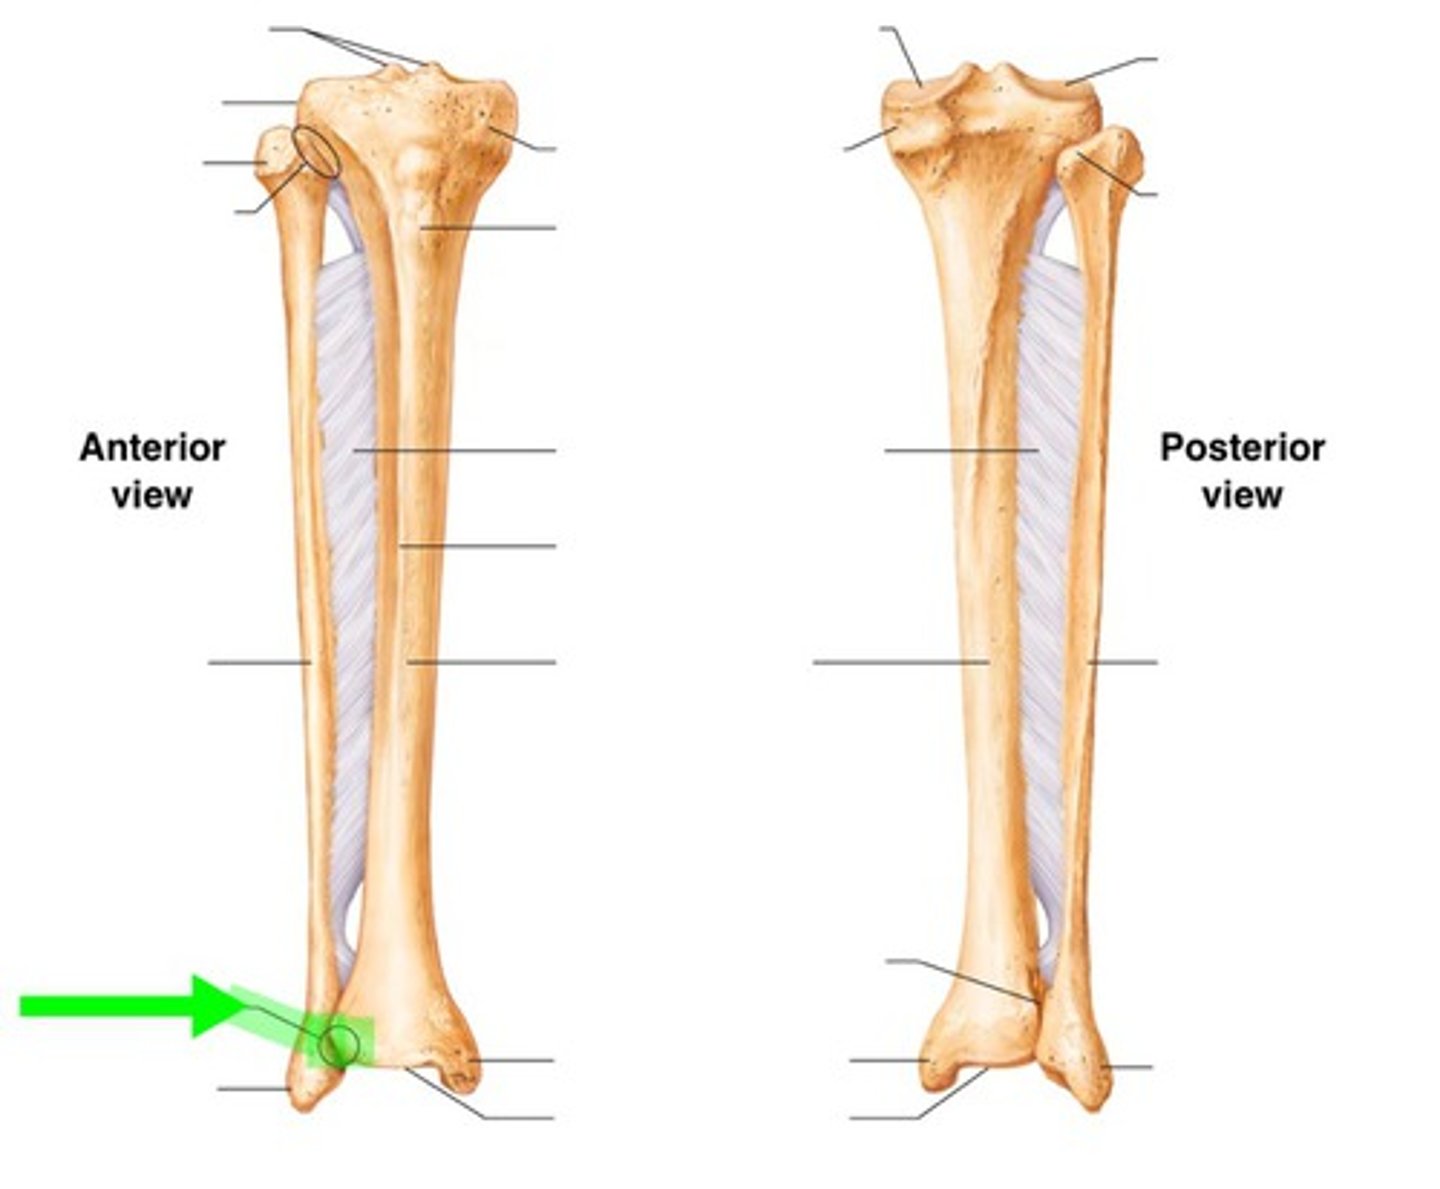

A majority of body weight is transferred through the (bone)

Tibia

What percentage of total body weight is transferred through the tibia?

90% total body weight